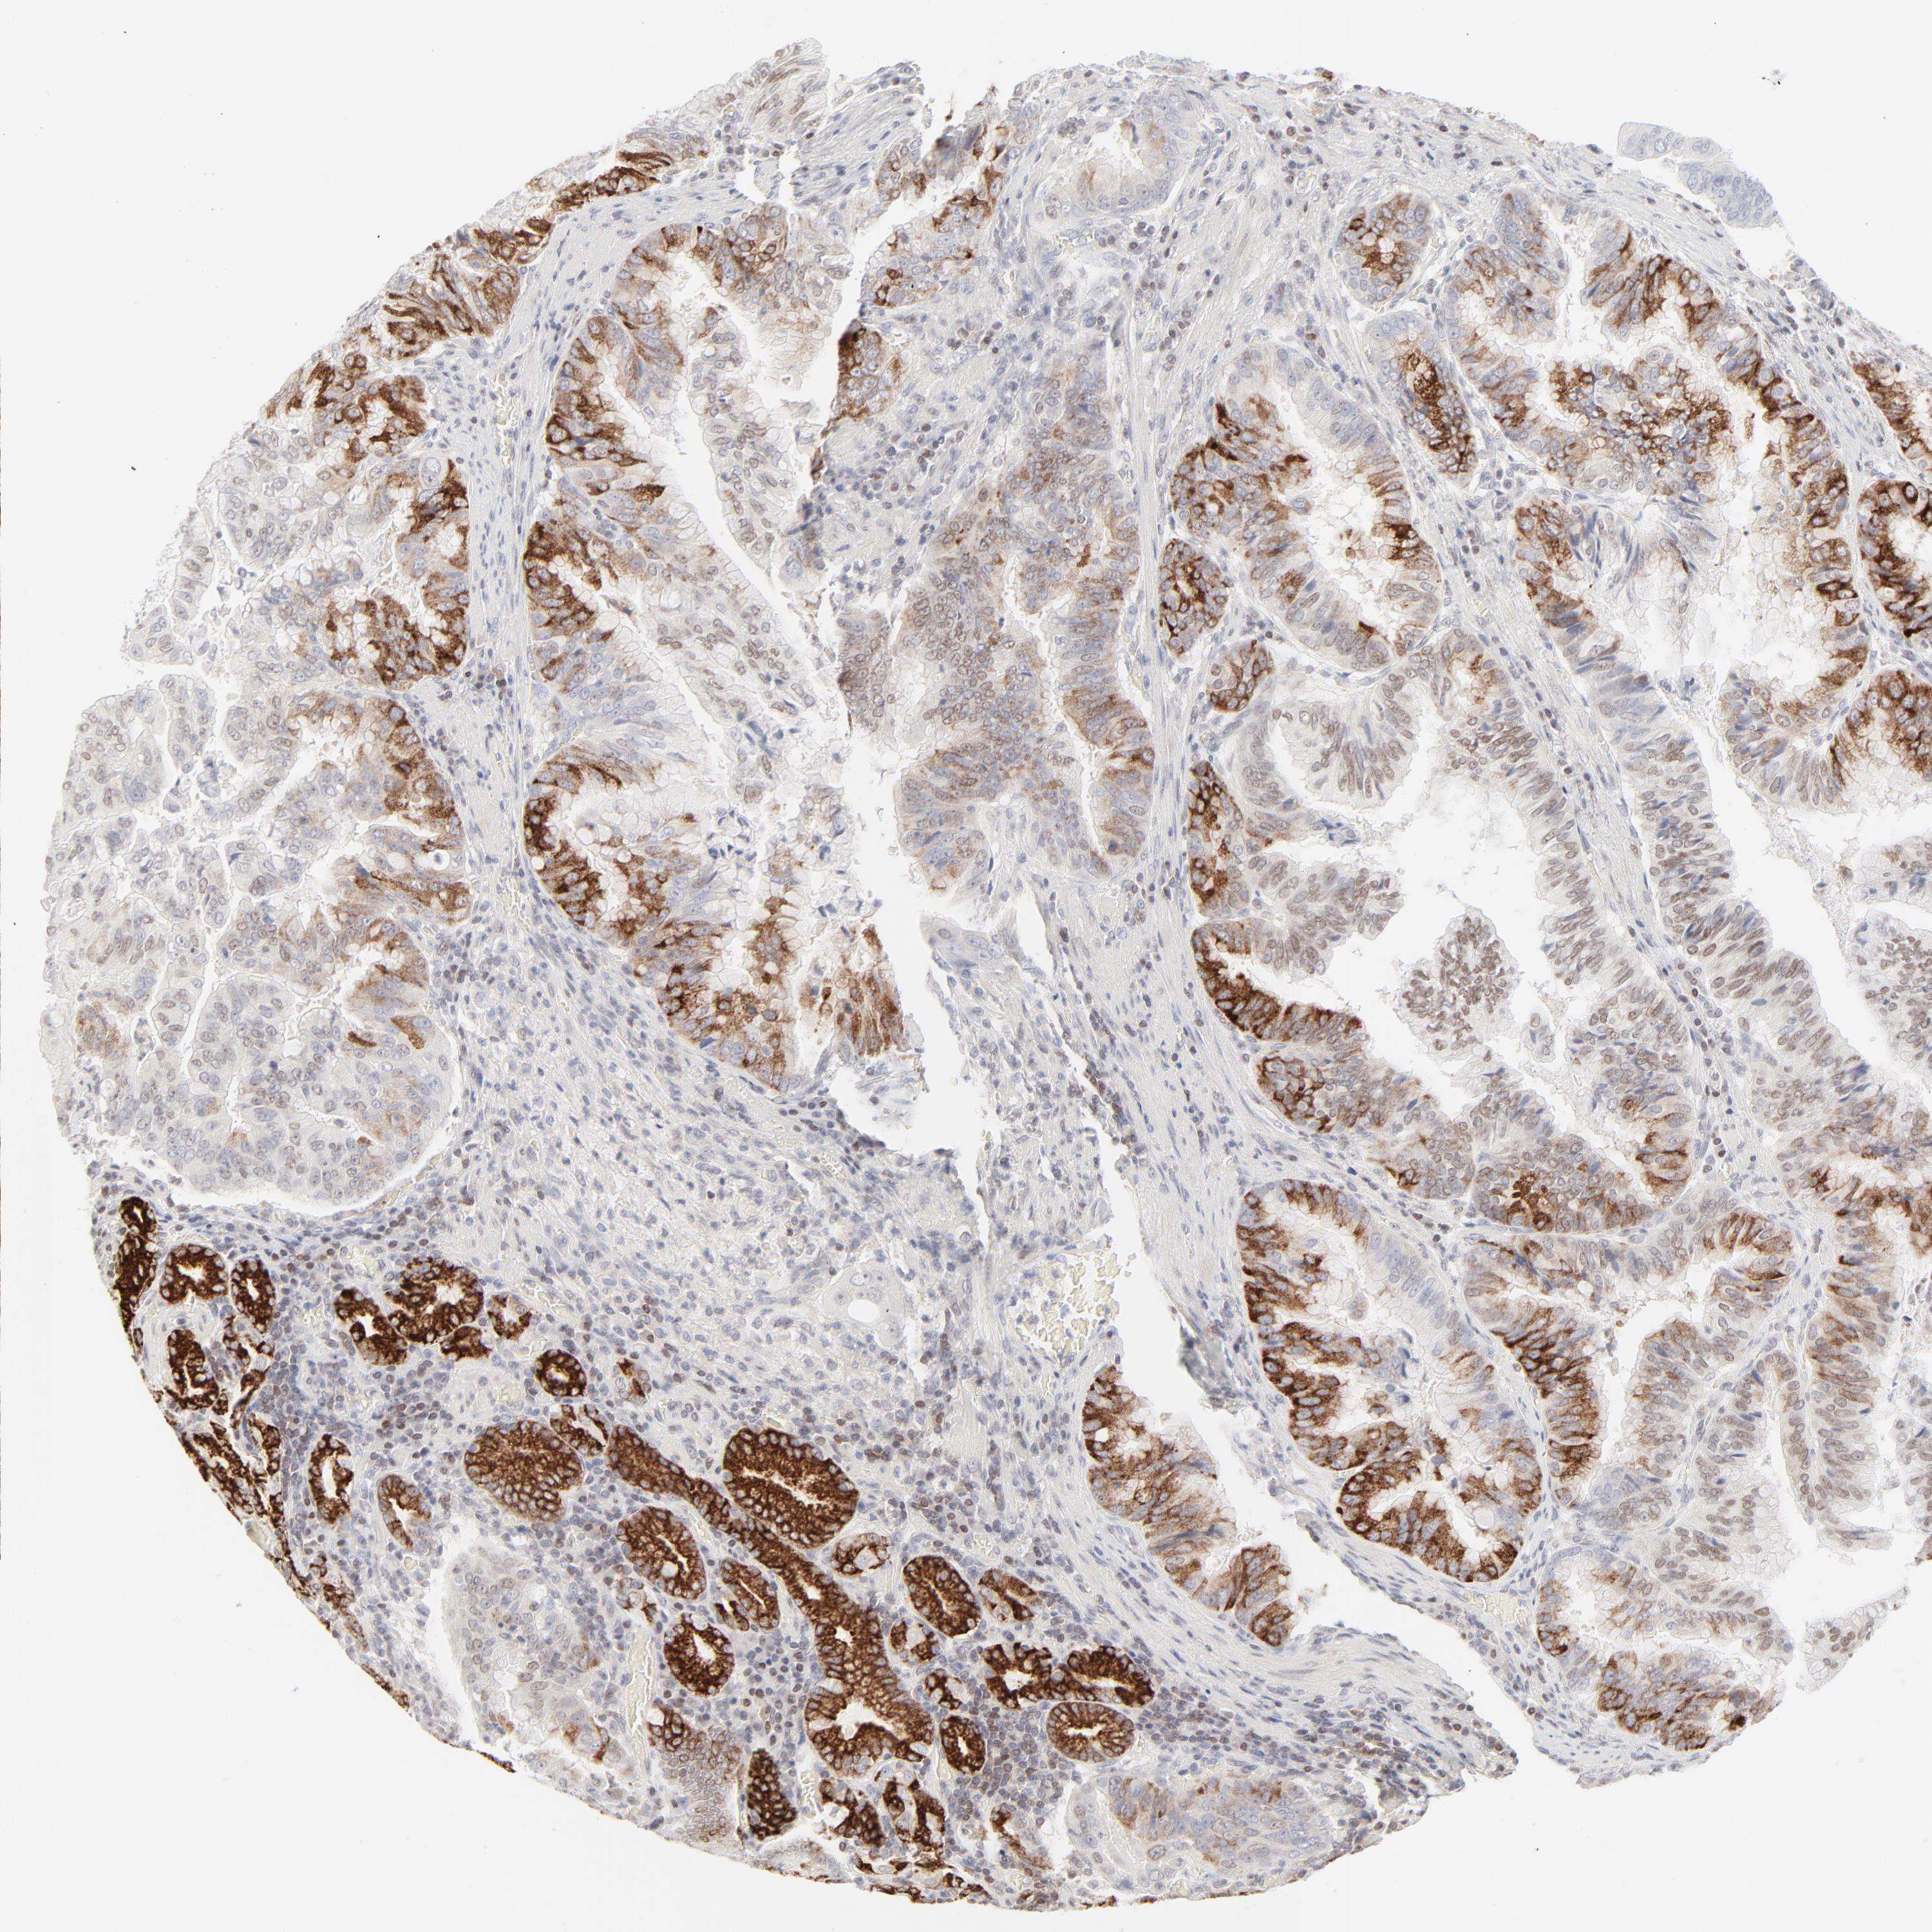

STOMACH CANCER - Protein expressioni

A mouse-over function shows sample information and annotation data. Click on an image to view it in a full screen mode. Samples can be filtered based on level of antibody staining by selecting one or several of the following categories: high, medium, low and not detected. The assay and annotation is described here.

Note that samples used for immunohistochemistry by the Human Protein Atlas do not correspond to samples in the TCGA dataset.

Antibody stainingi

Antibody staining in the annotated cell types in the current human tissue is reported as not detected, low, medium, or high, based on conventional immunohistochemistry profiling in selected tissues. This score is based on the combination of the staining intensity and fraction of stained cells.

Each image is clickable and will lead to virtual microscopy that enables deeper exploration of all samples and also displays staining intensity scores, fraction scores and subcellular localization as well as patient and tissue information for each sample.

Antibody HPA048321

Antibody CAB003843

Staining

High

Medium

Low

Not detected

Intensity

Strong

Moderate

Weak

Negative

Quantity

>75%

75%-25%

<25%

None

Location

Nuclear

Cytoplasmic/membranous

Cytoplasmic/membranous,nuclear

Adenocarcinoma, NOS